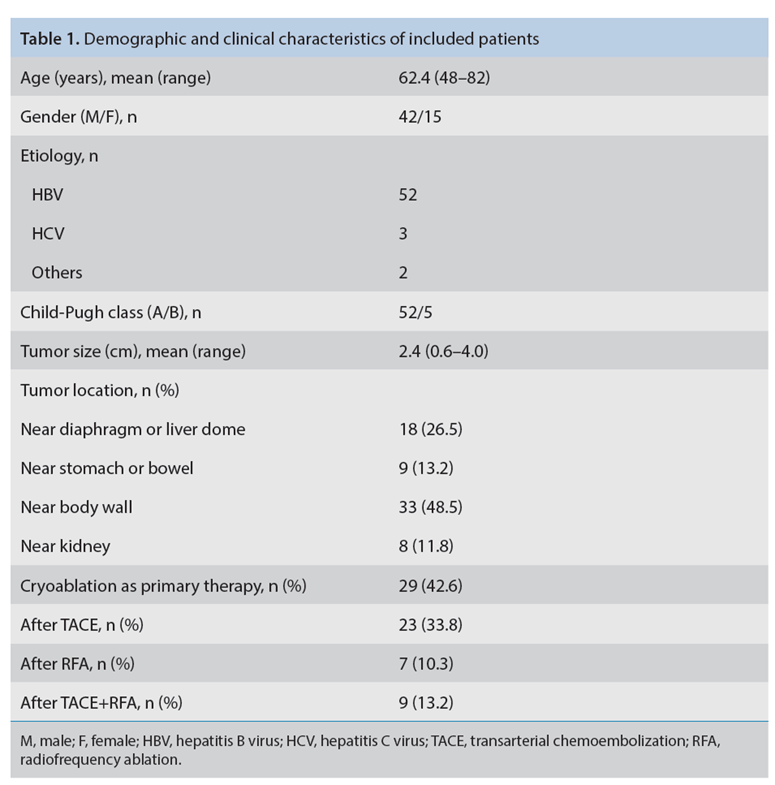

本研究中患者随访期间无局部肿瘤进展,无死亡病例,没有发现与手术相关的并发症。证实冷冻消融是一种有效的治疗方式,在技术上是可行和安全的。由于肝包膜下病变位置特殊,射频消融有出血及肿瘤种植的风险,可能会对邻近器官造成损伤,并且增加局部肿瘤进展的风险。近年来,冷冻消融术的应用逐渐广泛,有研究显示冷冻消融治疗具有明显优势,可治疗特殊部位的肝肿瘤。本研究的目的是评价冷冻消融治疗肝包膜下肿瘤的安全性和有效性。回顾性纳入2016年7月1日至2018年9月1日期间冷冻消融的57例患者。包括42例男性和15例女性,平均年龄为62.4岁(范围:48-82岁)。每个患者有1个或2个平均肿瘤尺寸为2.4cm的病变(范围:0.6-4.0cm)。所有患者均患有慢性肝病或肝硬化,并伴有乙型肝炎(n=52)、丙型肝炎(n=3)和其他肝炎(n=2)。根据肿瘤位置,在膈肌或肝脏下附近有18个病变(26.5%),胃或肠附近有9个病变(13.2%),腹壁附近有33个病变(48.5%),肾脏附近有8个病变(11.8%)。

入选标准:

(1) 最多3个直径5 cm的肿瘤病变;

(2) 肝功能分级Child-Pugh A/B级患者,无证据表明脏器粘连,无大血管浸润和肝外转移;

(3) 凝血功能:正常凝血酶原时间和血小板计数≥50000 cells/mL;

(4) 年龄<85岁;

完全消融率为97%(66/68);2名患者均接受了额外的冷冻消融,随后实现完全消融。平均随访期为 12.8 个月(范围:3-27 个月)。所有患者均接受影像复查(CT 或 MRI)。11个病灶(16.2%)检测到局部肿瘤进展,6、12和18个月时的累积局部肿瘤进展率分别为4%、8.2%和20.5%。8例出现远处肝内或肝外病变的患者接受经动脉化疗栓塞、经动脉化疗栓塞加射频消融治疗或全身化疗。

主要和次要并发症发生率分别为3.5%(2/57)和22.8%(13/57)。并发症主要表现为局部皮肤冻伤、中度气胸、发热,仅有少数患者接受治疗,多数患者自行恢复。所有患者能耐受围手术期疼痛,VAS 评分范围在 1-3 分之间(平均 1.65分)。3例患者术后疼痛加重,VAS评分达到4~5分,患者口服止痛药后逐渐缓解。所有患者术后1天血常规、白细胞计数均升高,血小板均有不同程度下降,但变化值均在正常范围内。肝功能1个月后逐渐恢复到正常水平。